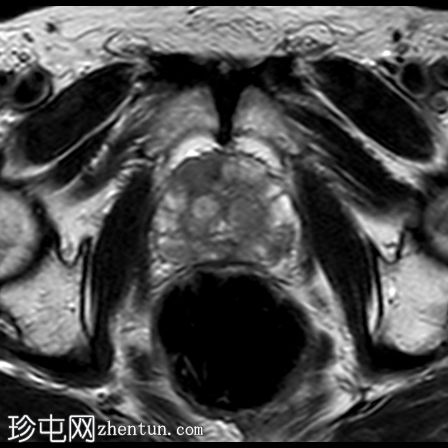

轴位

T2加权像

右侧前列腺前中带可见一边界不清的18 x 10 mm扁豆状病灶,T2加权像呈低信号,扩散受限(DWI高信号,ADC低信号),与周围实质相比早期强化,病灶位于前移行区与纤维肌性间质交界处。影像学表现符合PI-RADS 5级病灶。

未见前列腺外侵犯、盆腔淋巴结肿大或疑似骨病变。